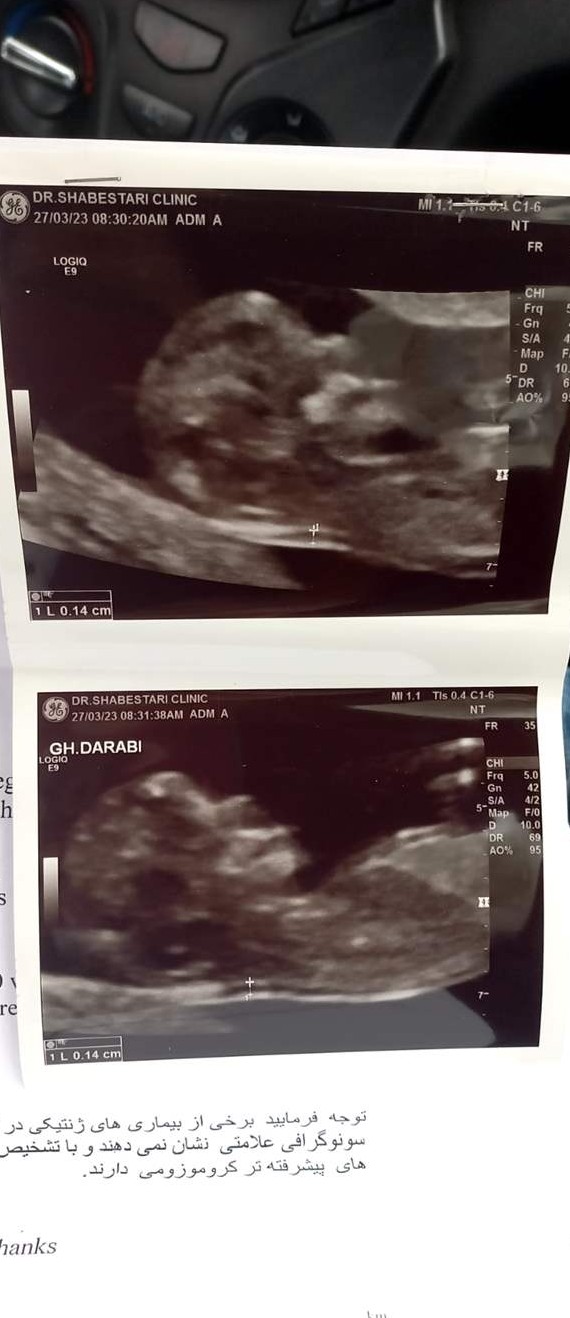

پیش بینی جنسیت جنین بر اساس شکل جمجمه و پیشانی می گوید جنین های پسر سر بزرگتری و پیشانی شیب دارتری دارند. دارای برجستگی مشخص ابرو، چانه مربع شکل و آرواره های زاویه دار تر هستند.